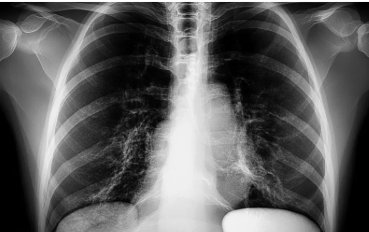

폐렴 증상의 병리적 진행 단계

혼탁기 (Congestion)

- 시기: 감염 후 24시간 이내

- 주요 증상: 기침, 미열, 흉부의 불쾌감

- 병리적 변화: 폐혈관이 확장되고 폐포에 삼출물이 축적되기 시작합니다.

적색 간화기 (Red Hepatization)

- 시기: 감염 후 2~4일

- 주요 증상: 심한 기침, 고열, 오한 등 증상이 뚜렷해집니다.

- 병리적 변화: 폐가 붉고 단단해지며 적혈구가 폐포 내에 축적됩니다.

회색 간화기 (Grey Hepatization)

- 시기: 감염 후 4~8일

- 주요 증상: 호흡곤란, 피로감이 지속됩니다.

- 병리적 변화: 적혈구가 파괴되며 섬유소가 침착되어 폐 조직이 회색으로 변화합니다.

해소기 (Resolution)

- 시기: 감염 후 8~10일 이후

- 주요 증상: 전반적인 증상이 완화되며 호흡이 정상으로 돌아옵니다.

- 병리적 변화: 폐의 염증이 흡수되면서 폐 기능이 점차 회복됩니다.